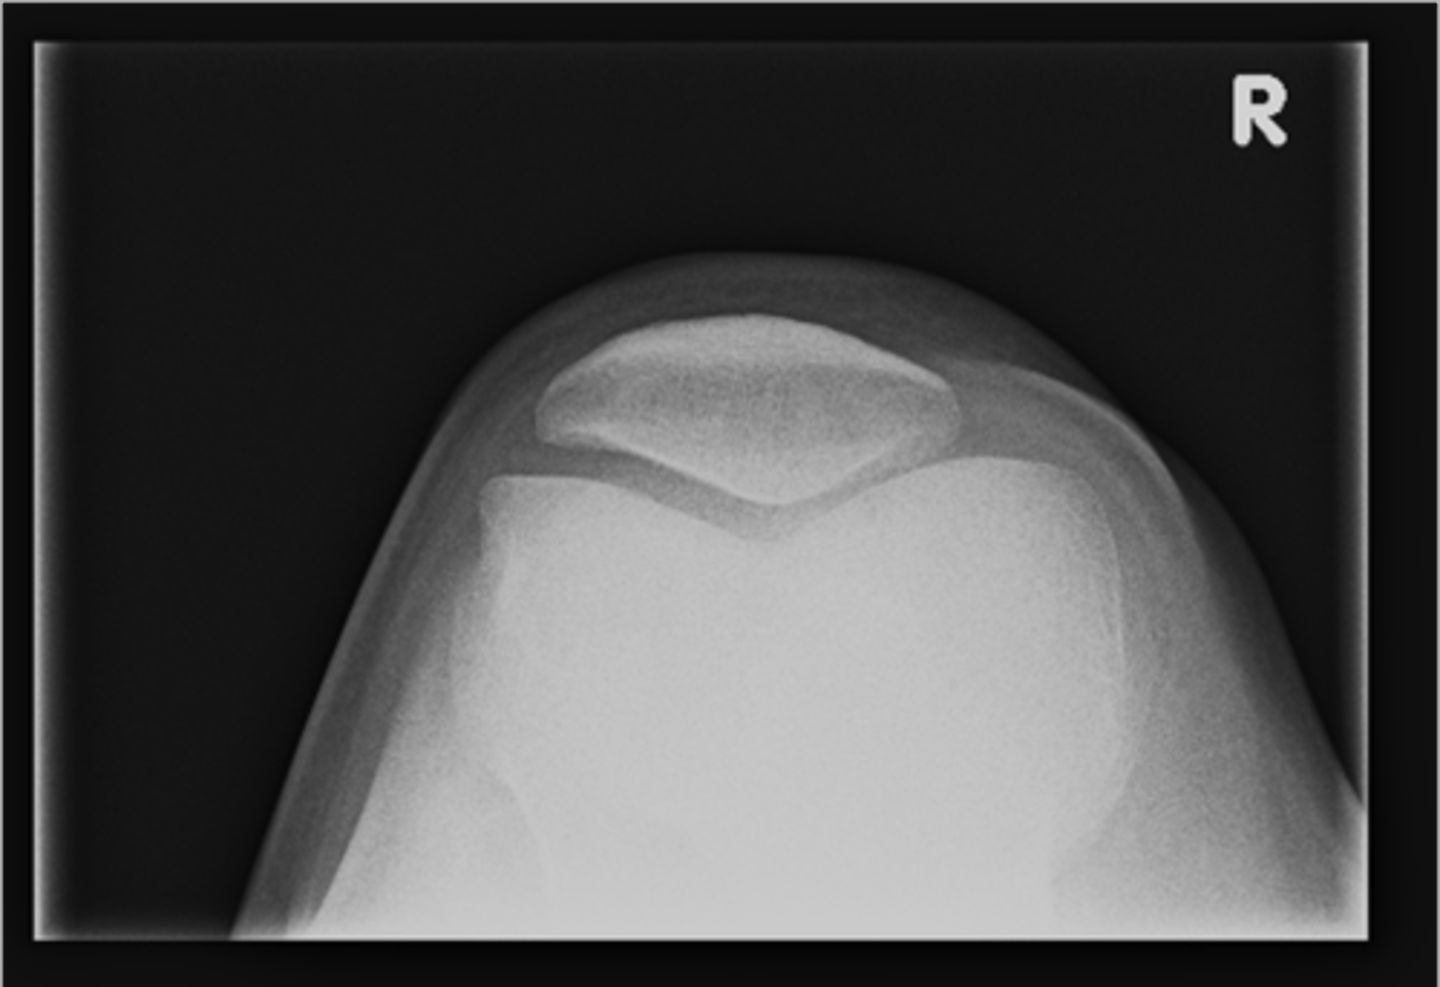

Sunrise (tangential) knee

ID supplementary knee projection

<p>ID supplementary knee projection</p>

Patellofemoral joints

Sunrise knee projections help see the _____

<p>Sunrise knee projections help see the _____</p>

Medial patellofemoral joint

ID 37 (joint)

<p>ID 37 (joint)</p>

Lateral patellofemoral joint

ID 38 (joint)

<p>ID 38 (joint)</p>

Odd facet

ID 39

<p>ID 39</p>